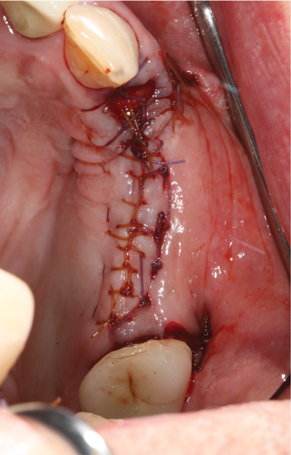

Fig 14. Two-week postoperative healing at maxillary left quadrant lateral ridge augmentation.

Figure 14